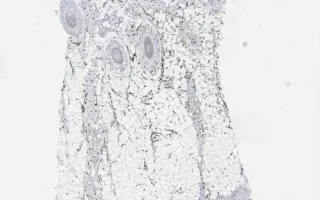

Skin, Cutaneous angiosarcoma, ERG stain

The biopsy shows irregular/atypical vascular spaces involving the superficial dermis with extension deeply and around adnexal structures. The vascular spaces are positive for ERG (vascular marker) and negative for HHV8 (ruling out Kaposi sarcoma).

This slide shows ERG stain stain. See Related Content for H&E and HHV8 stains.